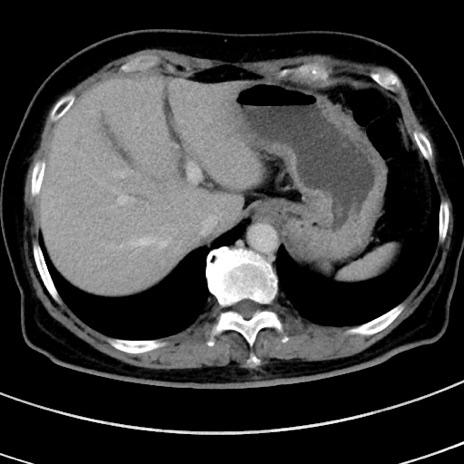

症例9(横断像)

【症例】 60歳代女性

【主訴】むかつき、みぞおちの痛み

【現病歴】3日前よりむかつきがあり、食事がとれない。

【既往歴】糖尿病

【身体所見】発熱なし、心窩部圧痛軽度あるも、腹膜刺激症状なし。

【データ】WBC 7400、CRP 1.92